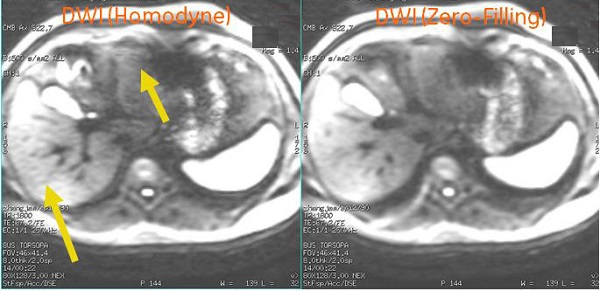

Worm hole

Diffusion Weighted Echo Planar Imaging uses partial k-space acquisition combined with homodyne reconstruction. When there is rotational motion in conjunction with the diffusion lobe, the k-space data is shifted by a large amount. This is the root cause of the wormhole-like artifact. The frequency in which the artifact appears increases at high b-values due to the use of higher and/or longer diffusion gradient lobes.